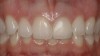

A 36-year-old nonsmoking Caucasian woman in good health presented to the author’s periodontal practice to replace tooth No. 26 with an implant. She had presented to her restorative dentist with a chief complaint of yellow, poorly color-matched mandibular anterior teeth (Figure 1). Her medical history was significant for asthma and seasonal allergies for which she took oral montelukast, orally inhaled fluticasone and salmeterol, and oral cetirizine; she also took lorazepam for anxiety. Her dental history was significant for traumatic experiences.

Figure 1  Initial presentation with yellow, poorly color-matched restored mandibular anterior teeth.

Figure 1